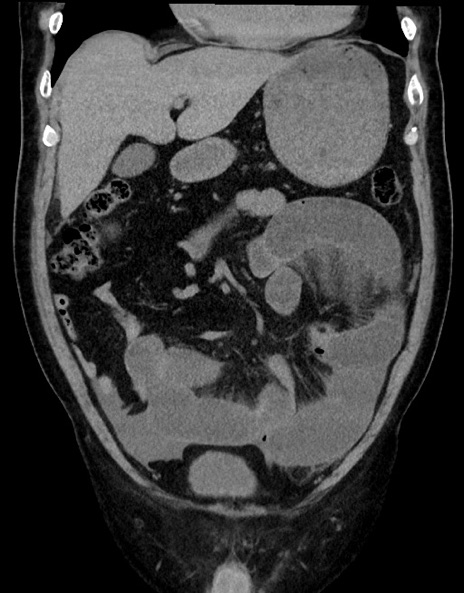

症例15(冠状断像)

【症例】70歳代男性

【主訴】腹痛

【現病歴】今朝から腹痛あり。全体的に痛い。特に左上の方。排ガスが今日はない。冷や汗が出る。

【既往歴】直腸癌術後

【身体所見】左側腹部〜上腹部に圧痛あり。腹膜刺激症状明らかなではない。軽度反跳痛。左下腹部に術後瘢痕あり。

【データ】WBC 7700、CRP 0.02